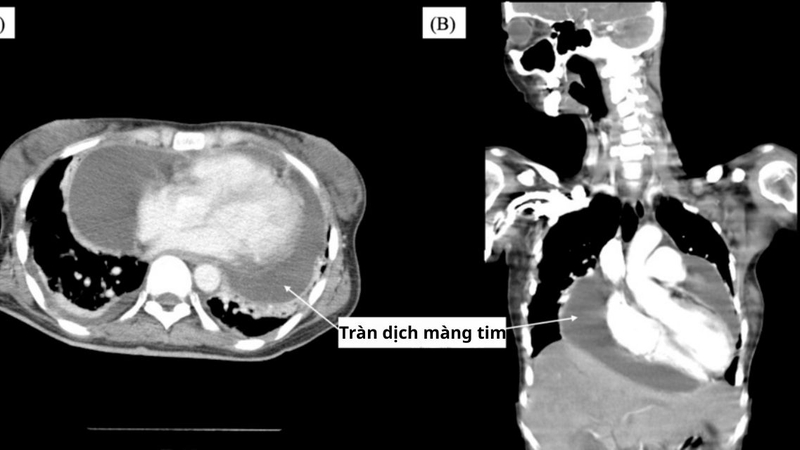

Lupus ban đỏ hệ thống có thể gây tràn dịch màng tim, và đây là một trong những biến chứng tim mạch tương đối thường gặp ở người bệnh. Mức độ tràn dịch có thể từ nhẹ, không triệu chứng cho đến nặng, có thể đe dọa tính mạng nếu không được phát hiện và xử trí kịp thời.

Lupus ban đỏ có gây tràn dịch màng tim không? Ở người bệnh lupus ban đỏ, hệ miễn dịch hoạt động quá mức và tấn công nhầm vào các mô của cơ thể, bao gồm cả màng tim. Quá trình viêm tại màng tim làm tăng tính thấm của mạch máu, khiến dịch viêm thoát ra và tích tụ trong khoang màng tim.

Các phức hợp miễn dịch hình thành trong lupus có thể lắng đọng tại màng tim, kích hoạt phản ứng viêm kéo dài. Phản ứng viêm làm tăng tính thấm thành mạch, khiến dịch viêm thoát vào khoang màng tim và tích tụ dần.

Tràn dịch màng tim có thể xuất hiện hoặc nặng lên trong các đợt lupus hoạt động mạnh. Khi hoạt động bệnh tăng cao, mức độ viêm toàn thân và tổn thương cơ quan cũng gia tăng, làm nguy cơ tích tụ dịch quanh tim cao hơn.